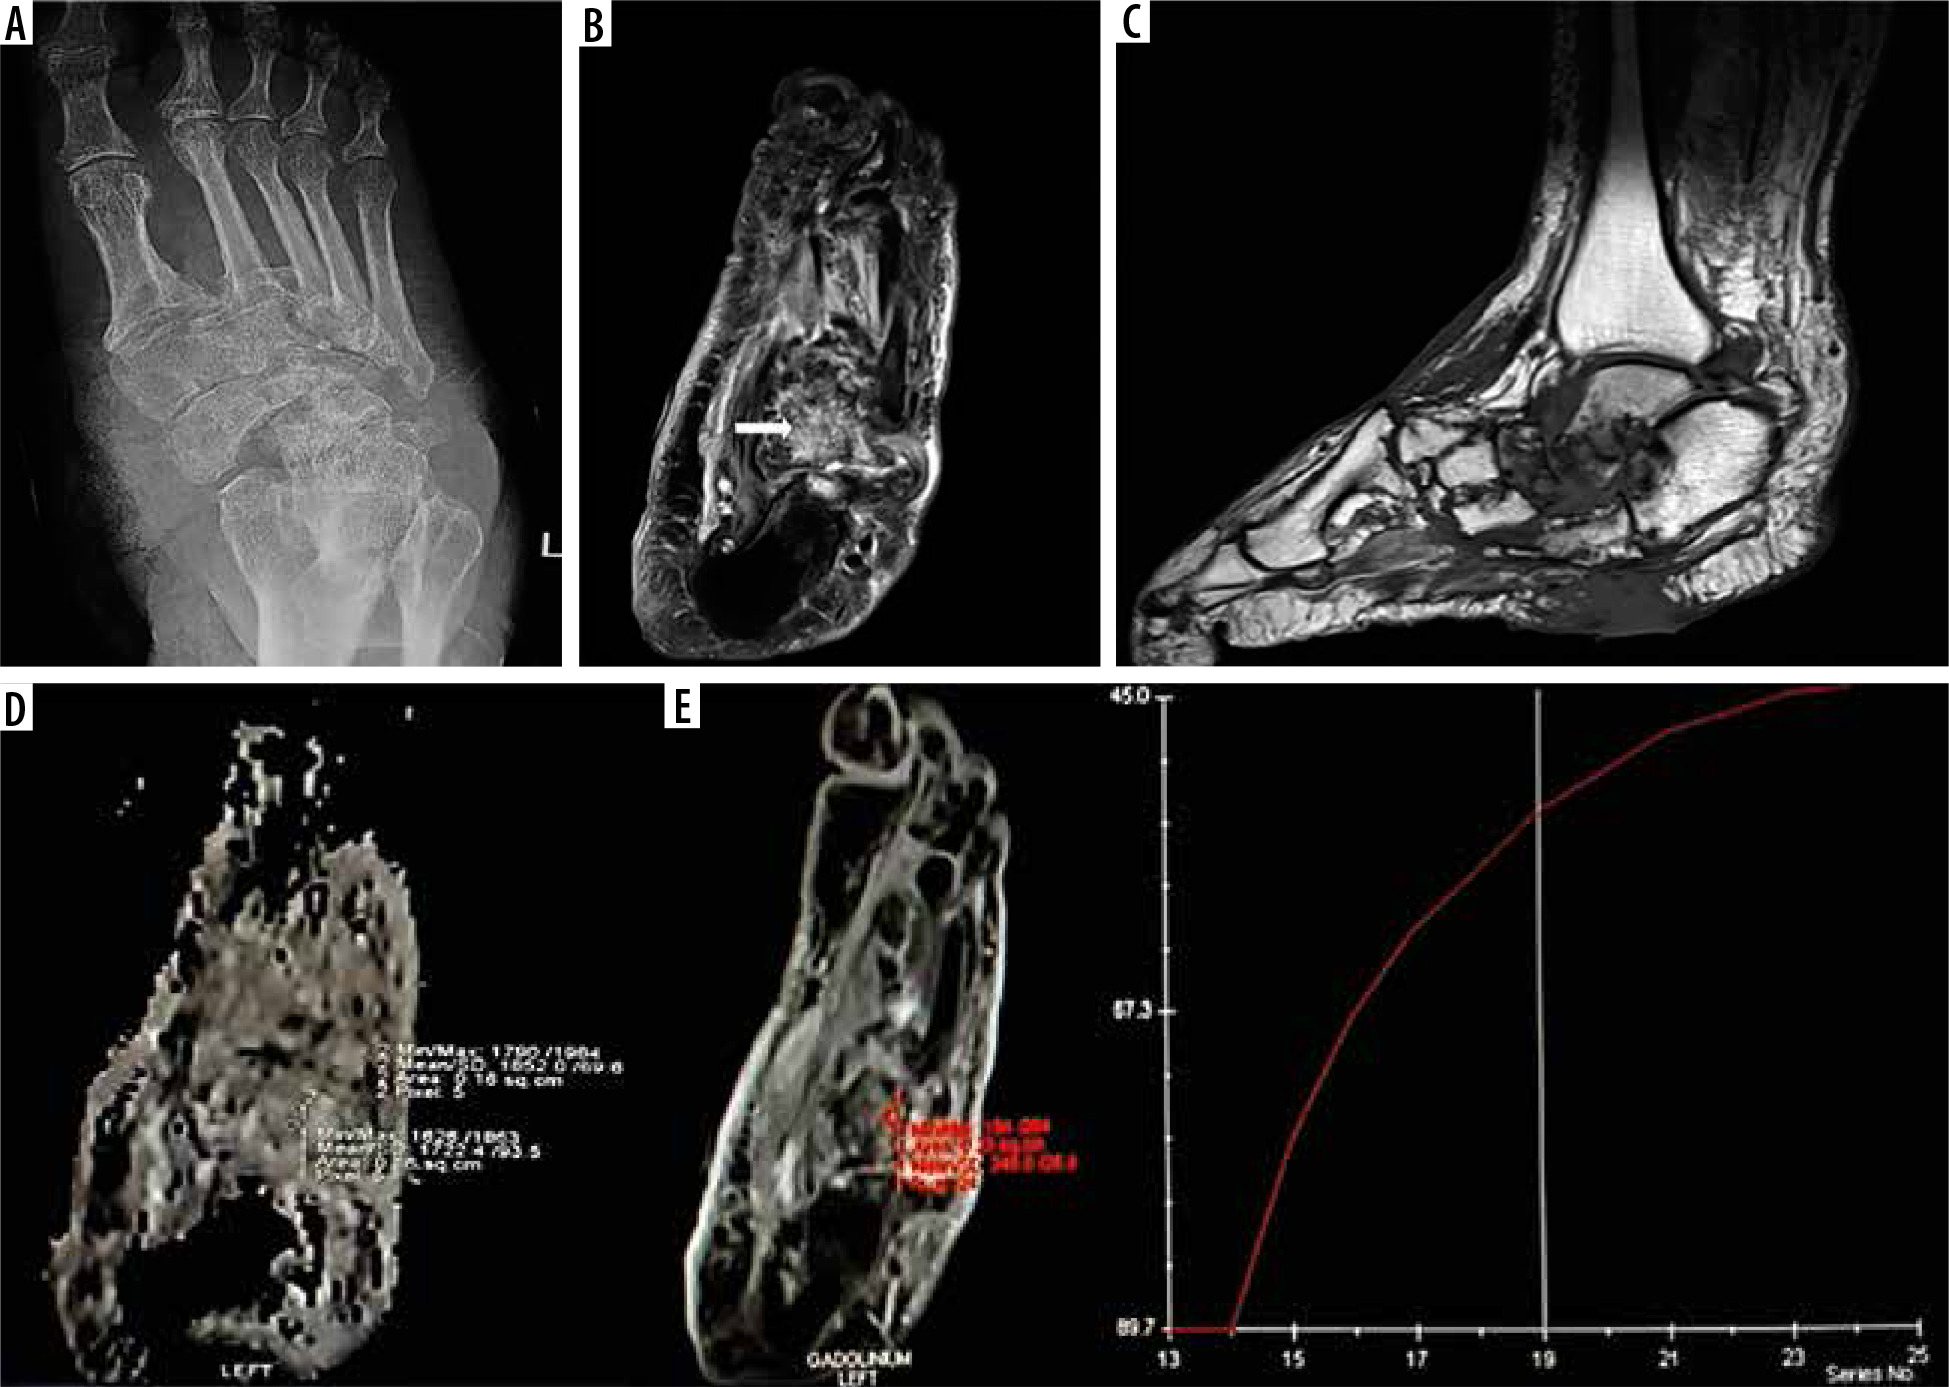

Figure 1

A 55-year-old diabetic female with non-healing ulcerations on the lateral aspect of the foot. Biopsy from the base of the 5th metatarsal revealed osteomyelitis. A) X-ray shows mild cortical irregularity with a solid periosteal reaction involving the base of the 5th metatarsal bone. B) Sagittal T2WI showing hyperintense signal involving the base of the 5th metatarsal (thick white arrow) with inflammatory changes in underlying soft tissue. C) Sagittal T1WI showing hypointense signal in the corresponding location. D) ADC map showing ADC value of 1.18 × 10-3 mm2/s (ROI drawn over the base of 5th metatarsal). E) Dynamic post-contrast enhancement showing type II curve, SI0 – 171.1, SImax – 544